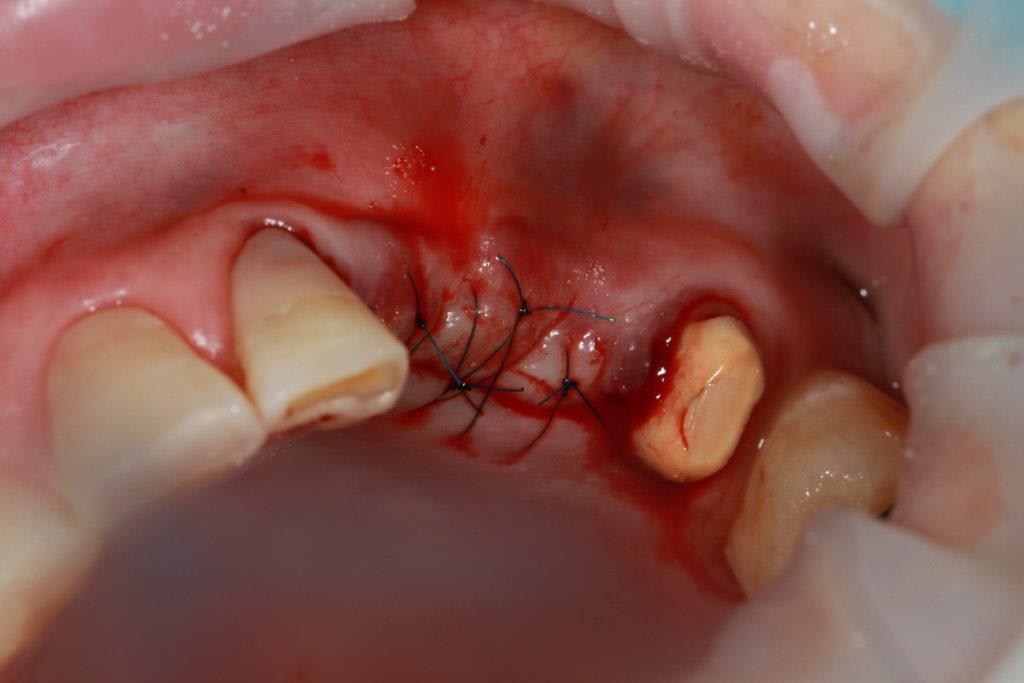

petit cas sympa ancien bridge très mobile....plutôt que d'extraire 25, j'ai déposé la couronne, retraité la dent stabilisation pendant deux mois puis séance d'ostéotension et ce jour pose de deux axioms PX 34120 après expansion...

non, uniquement travail par voie crestale, très légère fêlure niveau 23, mais sans conséquence

comme je n'ai pas fait de décharges osseuse en vestibulaire, j'ai effectivement travaillé toute la longueur de la crête, mais, là j'ai ôtè les expanseurs avant de visser les implants car ce sont des PX qui ont un apex assez fin, pour des regular j'aurais pratiqué différemment.

en général (99,9% des cas) je ne constate aucune lyse osseusecrestale, ce type de chir. est très douce pour l'os, lame 15, et ostéotomes, pas de forage, pas de consommation d'os, pas d'agression ni de lavage (piezzo), et je fais toujours attention à laisser du sang (sauf pour les photos) ce qui est le meilleur pansement pour l'os.

par contre les axioms doivent être posé en sous crestal, ce qui est fait ici, avec sans doute comme souvent une nécessitè d’ostéotomie, lors de la mise en charge, car il est fréquent que le col implantaire soit recouvert.